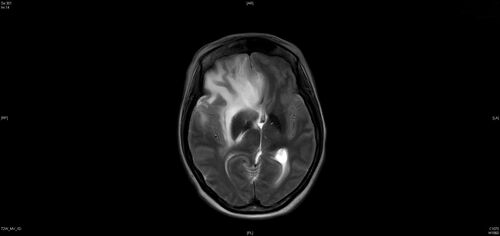

Coats Plus Syndrome - Cerebroretinal microangiopathy with calcifications and cysts (CRMCC)

38 year old female CTC1 positive with Coats Plus Syndrome. This case was published https://pmc.ncbi.nlm.nih.gov/articles/PMC10649444/